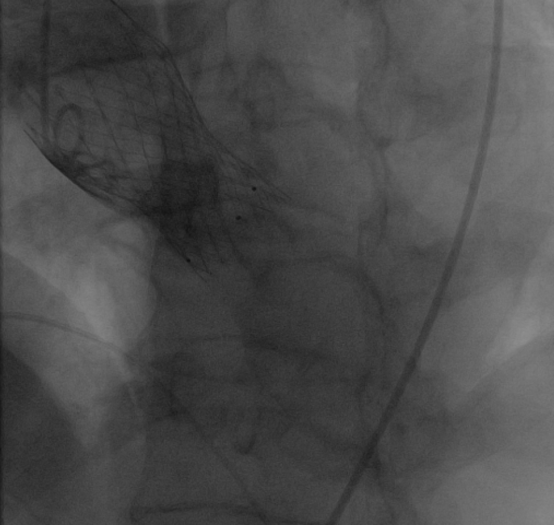

12月31日首都医科大学附属北京同仁医院心血管中心郭彩霞教授团队顺利完成首例TAVR手术。术中22mm球囊预扩冠脉不显影随即进行左冠冠脉烟囱支架保护,植入VenusA Plus可回收L26瓣膜,植入后位置良好,跨瓣压差近乎为零,整个手术一气呵成,手术取得圆满成功,手术后患者状态良好,成功救治82岁高龄患者。体现了心血管中心团队的综合救治能力,标志着在结构性心脏病的微创治疗方面达到国内先进水平。